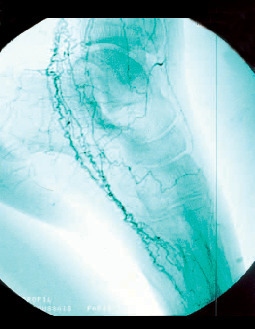

L’imagerie met en évidence une atteinte occlusive segmentaire des artères de petit et moyen calibres, initialement des artères digitales. La présence d’une circulation collatérale est fréquente, entraînant un aspect tortueux avec des images en « tire-bouchon » (fig. 18). Les artères proximales sont normales. L’arrêt du tabac est indispensable. L’iloprost (analogue des prostacyclines) améliore les lésions ischémiques distales.